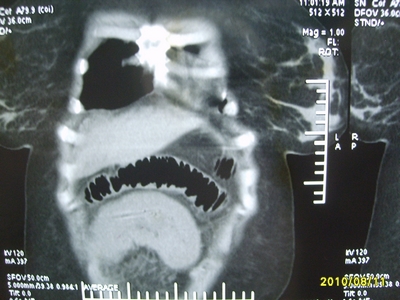

5天前突发腹痛剧烈难忍,伴解淡血水样便。近一天来腹痛缓解,没有明显的腹膜炎的体征。今天照的腹部ct。从ct上看感觉是一个绞窄性肠梗阻,但是现在没有腹痛。不好解释

请放射科的专家,帮帮看看。从影像学的角度来看看。这是不是一个绞窄性肠梗阻。

要有麻烦了,感觉小肠有套叠还有扭转改变,估计部分已有坏死。

高位肠梗阻(不全性),原因小肠(空肠)扭转,肠壁水肿增厚,成年人肠梗阻要排除合并占位,建议手术。

绞窄性肠梗阻_肠管套叠 扭转,肠壁明显水肿。

病人现在没有腹痛。怪了。从影像上来看。确实是绞窄了。但是没有腹痛。没有明显的腹膜炎的体征。确实有不好解释。难道是坏死了。反而不痛了。怪怪怪

支持绞窄性肠梗阻,肠壁明显水肿并见有多发小泡状积气--肠坏死

考虑绞窄性肠梗阻并肠坏死。